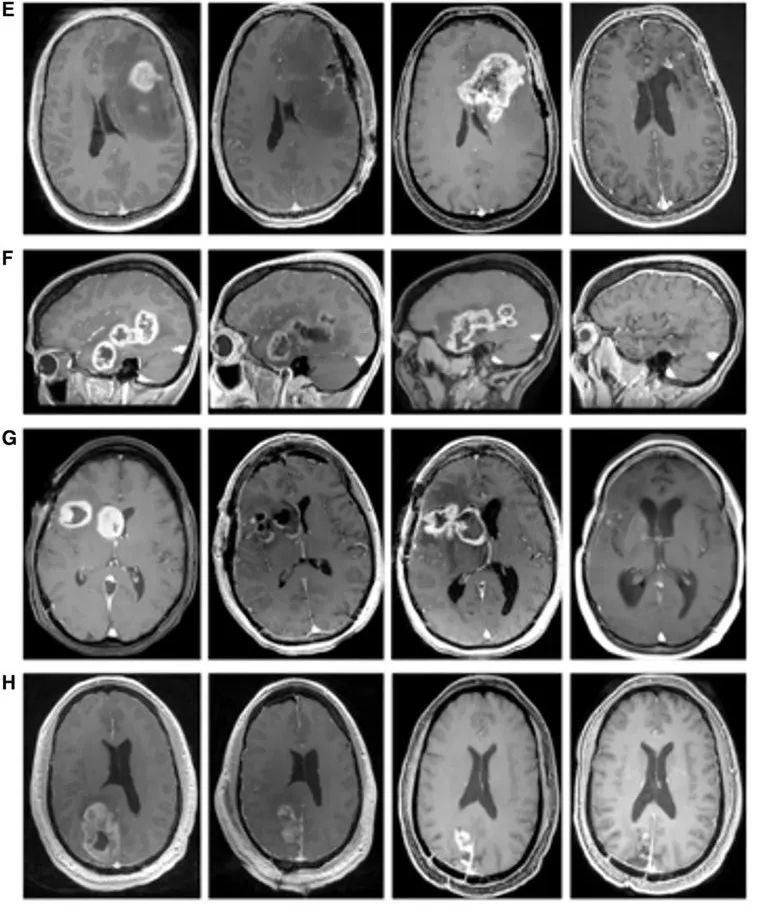

治疗效果呈现明确获益:CT检查显示,治疗前患者右下肺原发病灶伴胸腔积液,治疗114天后原发灶几乎消失;治疗第213天时虽出现复发迹象,但338天后复查可见复发灶缩小(详见下图)。

▲图源“Cureus”,版权归作者所有,如无意中侵犯了知识产权,请联系我们删除